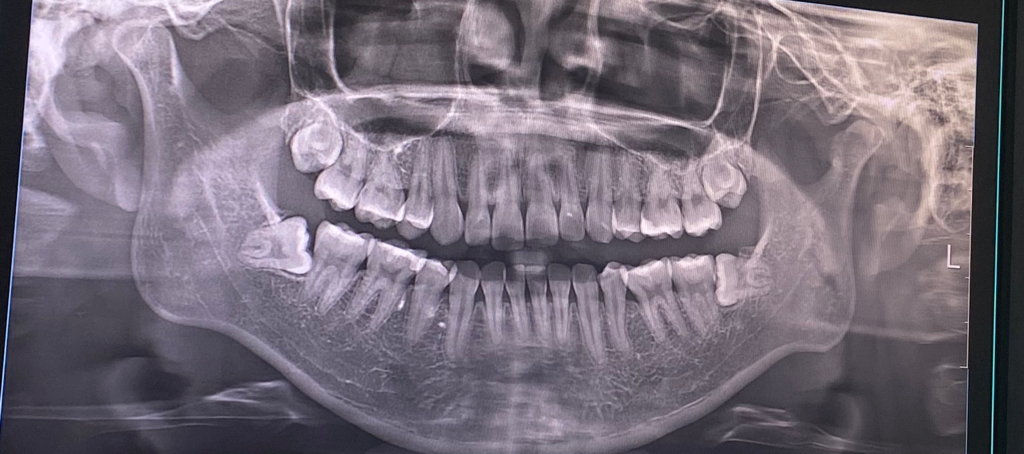

매복 사랑니 발치 시 뼈 삭제 필요할까요?

왼쪽 하악, 상악 사랑니 발치를 앞두고 있습니다. 오른쪽은 5월에 발치 했구요! 오른쪽은 잇몸에 덮여있었는데, 왼쪽은 살짝 끝에 매복사랑니가 보여요.

이럴 경우도 뼈 삭제 가능성이 있을까요?

왼쪽 아래 사랑니는 수평 매복 사랑니로 치아를 부수고 뼈도 삭제해야 발치할 수 있을 것으로 보입니다.

왼쪽 위의 사랑니도 매복되어 뼈삭제 할 수도, 혹은 하지 않고 할 수도 있습니다.